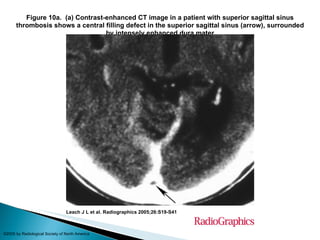

Figure 10a.  (a) Contrast-enhanced CT image in a patient with superior sagittal sinus thrombosis shows a central filling defect in the superior sagittal sinus (arrow), surrounded by intensely enhanced dura mater Leach J L et al. Radiographics 2005;26:S19-S41 ©2005 by Radiological Society of North America

Figure 10a.  (a) Contrast-enhancedCT image in a patient with superior sagittal sinus thrombosis shows a central filling defect in the superior sagittal sinus (arrow), surrounded by intensely enhanced dura mater Leach J L et al. Radiographics 2005;26:S19-S41 ©2005 by Radiological Society of North America

• #50 Figure 10a.  (a) Contrast-enhanced CT image in a patient with superior sagittal sinus thrombosis shows a central filling defect in the superior sagittal sinus (arrow), surrounded by intensely enhanced dura mater. (b) Coronal reformatted image from contrast-enhanced MR venography in another patient shows a nonenhanced thrombus (arrows) surrounded by enhanced sinus walls and dural cavernous spaces. The thrombus extends from the superior sagittal sinus through the sinus confluence and into the right transverse sinus.